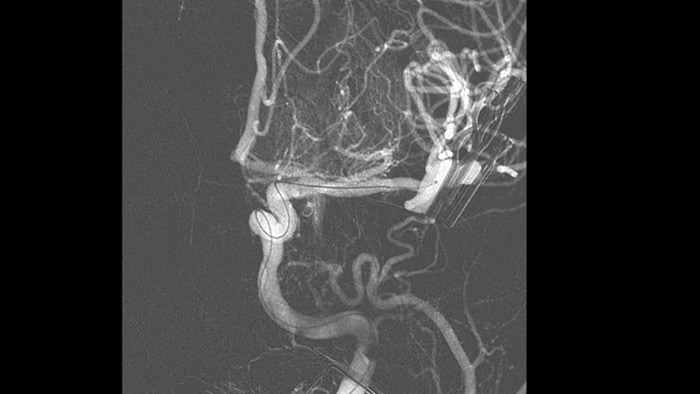

正確な3Dナビゲーションを支援する解剖学的リファレンス

SmartCT image

SmartCT Roadmapでは、ガイドワイヤ、カテーテル、およびデバイスの正確なナビゲーションをサポートする解剖学的なリファレンスを提供します。

治療の効果を確認

DSAの視覚化 image

高品質のDSA画像により、血栓が完全に回収されたかどうか、血栓の断片が脳内で遠位に分散しているかどうかを評価できます。また、ペナンブラへの血流の回復を確認し、治療前後の血流のチェックをすることができます。